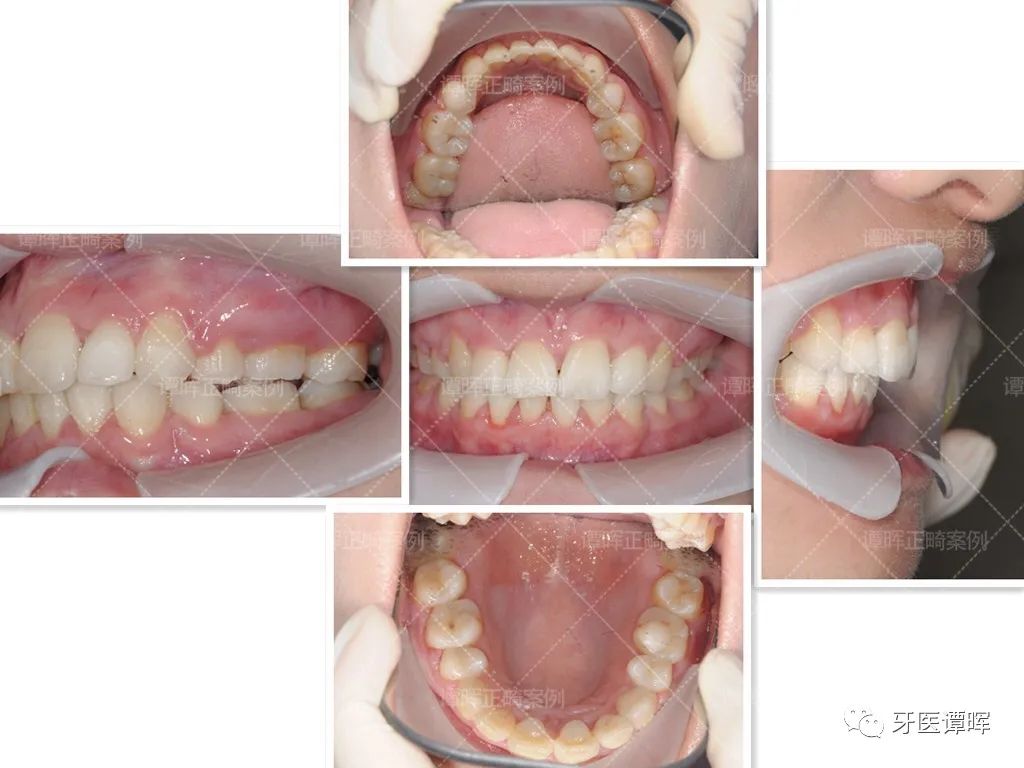

矫正后

全部牙套戴完,终于毕业啦!惊叹牙套神奇的魔力!所有牙齿得到归齐,从美美的笑容图开始看看效果~

从口内照可以看出,牙齿矫正后简直是大逆袭,花了一年半的时间,牙齿即排齐。总之,只要努力就可以改变一切。

从X线分析图可以明显看出前牙往前突内收,上牙的侧切牙也已排齐,牙列排齐。

从前的她不敢大笑,而且笑起来总是不自然,但现在的她敢露牙大笑。不仅门牙排列整齐,正面微笑脸型也更加柔和了。